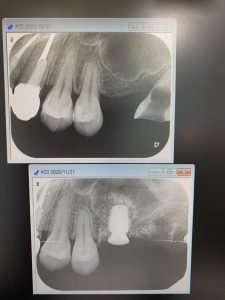

午前は矯正科の依頼を受け、左上に1本ソケットリフトインプラントを埋入。

歯周病や歯の喪失で歯槽骨が必要以上に痩せている場合、インプラントを埋入することが難しいため、この方法がにより歯槽骨の高さ(深さ)を増大する必要があります。

十分な挙上量も得られ、直径6長さ7ミリディープスレットインプラント体を埋入しました。